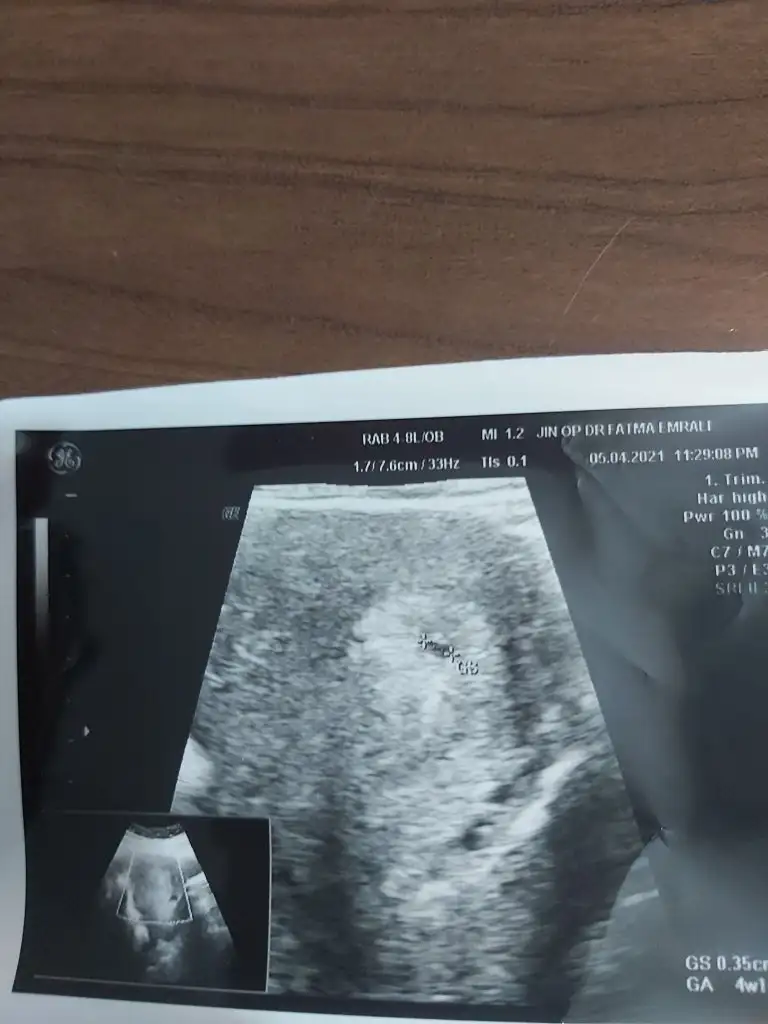

Kimse yok mu 😃 5+0

Eklentiler

• 20210405_165316.webp

20210405_165316.webp

28,7 KB · Görüntüleme: 99